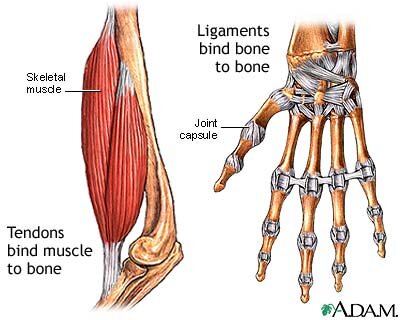

A Tendon attaches muscles to bones.

A Ligament attaches bone to bone.

And tendons and ligaments don’t have a blood supply like muscles do, hence they take such a long time to heal once injured…Even longer than a broken bone in most cases.